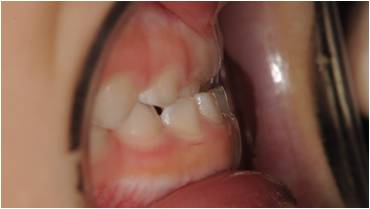

治療前

受け口の小児矯正治療(7歳の女子)の治療前後の写真です。矯正治療によって下顎前突(受け口)と上顎の狭さが改善され、正しい咬合に導かれています。